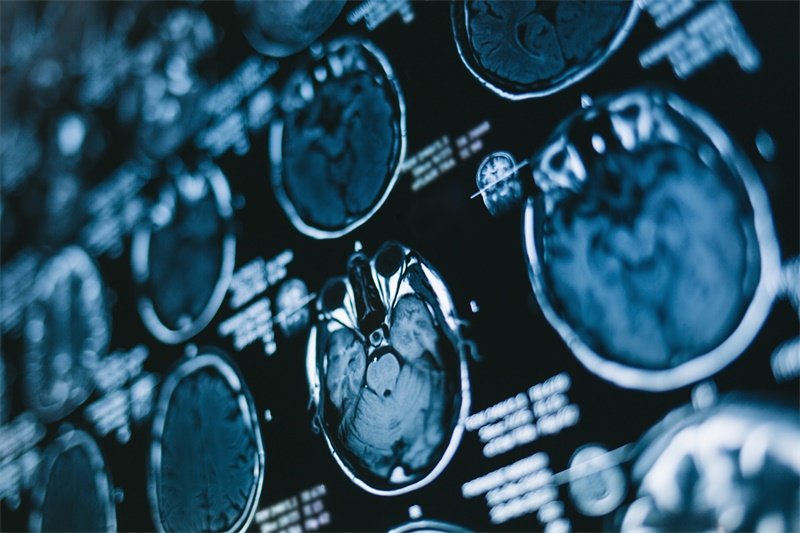

诊断垂体瘤主要依赖影像学检查,如MRI或CT扫描。这些检查可以帮助医生观察肿瘤的大小、位置及对周围组织的影响。